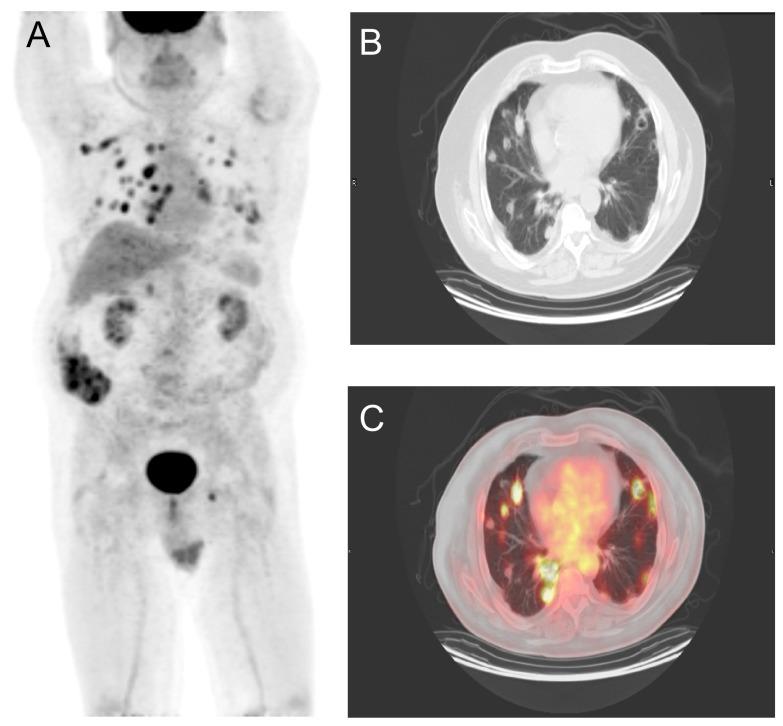

Presented is a 62-year-old Caucasian male with oculocutaneous albinism and a history of basal cell carcinomas occurring in multiple anatomic sites, most recently at the bilateral forearm and back.  Surveillance PET/CT imaging led to the discovery of no less than 30 lung nodules which were consistent with basal cell carcinoma on biopsy.  Histological features were remarkably similar in both the primary tumor and in the metastases.

An unusual case of a non-head and neck primary basal cell carcinoma metastatic to the lung was discovered on surveillance PET/CT imaging, in a patient with oculocutaneous albinism.

本文报告一名62岁患有眼皮肤白化病的白种男性,其多个解剖部位曾发生基底细胞癌,最近一次出现在双侧前臂和背部。监测性PET/CT成像发现不少于30个肺结节,活检显示这些结节与基底细胞癌相符。原发性肿瘤和转移灶的组织学特征非常相似。

在一名患有眼皮肤白化病的患者中,通过监测性PET/CT成像发现了一例罕见的非头颈部原发性基底细胞癌转移至肺部的病例。